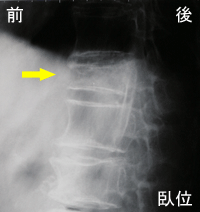

右のレントゲン像では矢印の椎体に圧迫骨折があります。これは圧迫骨

折がおこってから時間が経過して固くなった状態(骨硬化した状態)で

す。ここまで骨硬化して腰椎が安定すると圧迫骨折自体の痛みは無くなり

圧迫骨折が起こって最初からこのような形になるわけではなく、

最初はレントゲンで見ても変形が分りません。1〜2カ月かけて、

右図のように徐々に変形が進んでゆきます。